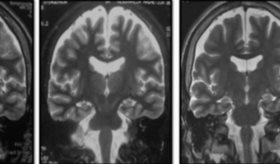

Para evaluar los efectos, se midieron las respuestas cerebrales mediante imágenes de resonancia magnética funcional, así como los niveles hormonales y las sensaciones subjetivas de hambre antes y después de la ingesta.

Los resultados, como señala el portal Intramed, mostraron que el consumo agudo de sucralosa, en comparación con la sacarosa, produjo un aumento del flujo sanguíneo en el hipotálamo (p<0,018), una mayor sensación de hambre (p<0,001) y ausencia de respuesta hormonal de saciedad. En términos generales, los hallazgos pueden interpretarse en las siguientes direcciones: